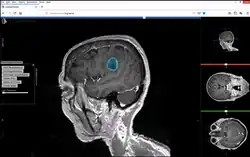

Studierfenster or StudierFenster (SF)[1][2][3] is a free, non-commercial open science client/server-based medical imaging processing online framework. It offers capabilities, like viewing medical data (computed tomography (CT), magnetic resonance imaging (MRI), etc.) in two- and three-dimensional space directly in the standard web browsers, like Google Chrome, Mozilla Firefox, Safari, and Microsoft Edge. Other functionalities are the calculation of medical metrics (dice score[4] and Hausdorff distance[5]), manual slice-by-slice outlining of structures in medical images (segmentation[6][7]), manual placing of (anatomical) landmarks in medical image data, viewing medical data in virtual reality, a facial reconstruction and registration of medical data for augmented reality,[8] one click showcases for COVID-19 and veterinary scans, and a Radiomics module.

Other features of Studierfenster are the automatic cranial implant design with a neural network,[9][10] the inpainting of aortic dissections[11] with a generative adversarial network,[12][13] an automatic aortic landmark detection with deep learning[14] in computed tomography angiography scans, and a GrowCut algorithm implementation for image segmentation.